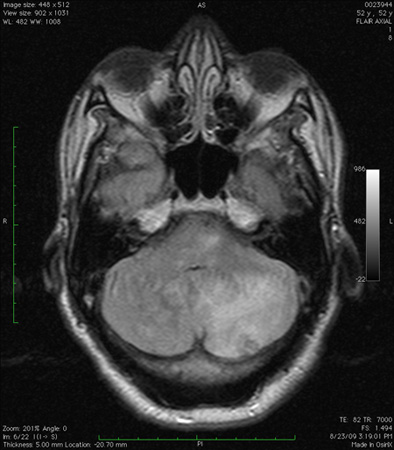

[Figure caption and citation for the preceding image starts]: Cerebellar infarct as seen on fluid-attenuated inversion recovery sequence magnetic resonance image: note secondary oedema and effacement of the fourth ventricleFrom the collection of Dr S. H. Subramony; used with permission [Citation ends].